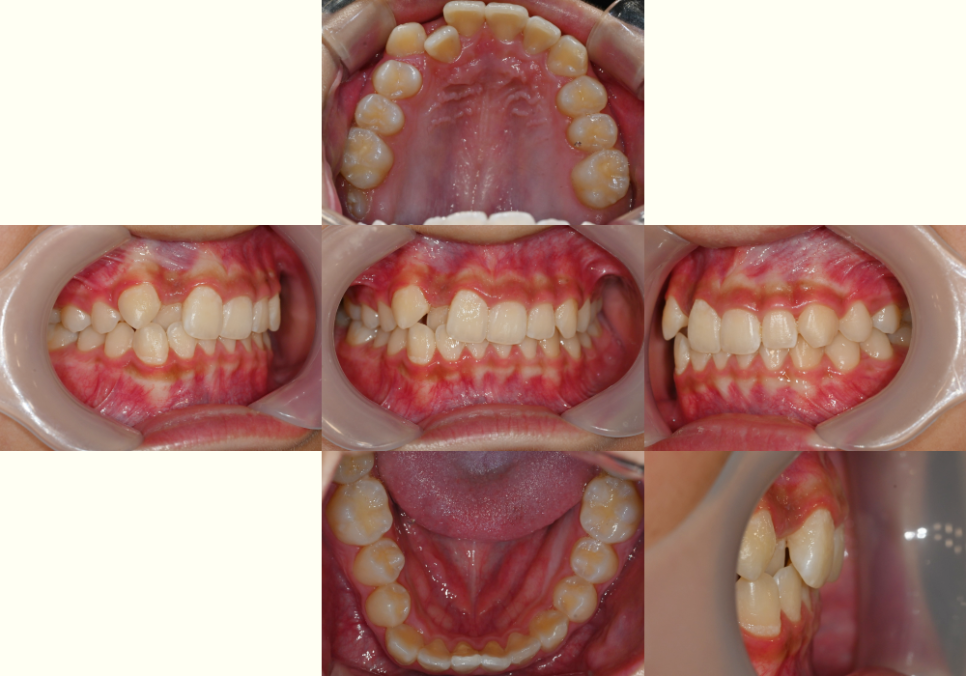

구강 내 모습을 보면

위아래 치열이 삐뚤빼뚤하며

윗니가 아랫니의 1/2~2/3 이상

덮어있는 과개교합(deep bite)으로

보였습니다.

더불어, 치아 사이 치석과 구강 위생 상태가

좋지 않아 본격적인 교정 전 스케일링과

구강 관리 교육을 우선 시행이 필요해 보였습니다.